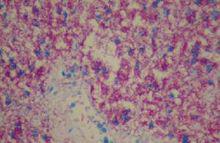

巨噬細胞破裂後,此色素也可見於細胞外。含鐵血黃素因含Fe3+而被普魯氏藍染成藍色。LaihoK報導,在人體,損傷出血後21~48h皮膚和皮下出現噬鐵細胞,4~8天后則多。BetzP等通過研究人體皮膚損傷標本認為,含鐵血黃素最早於傷後3天檢測到,傷後8天則超過顯微鏡20%的區域均可見含鐵血黃素沉積。據此認為只要20%或以上的檢測區域檢見含鐵血黃素沉積,就可認定損傷時間大約為7天。因此,通過圖像分析系統檢測巨噬細胞吞噬物推斷損傷時間有可能成為一種非常簡便易行的方法。